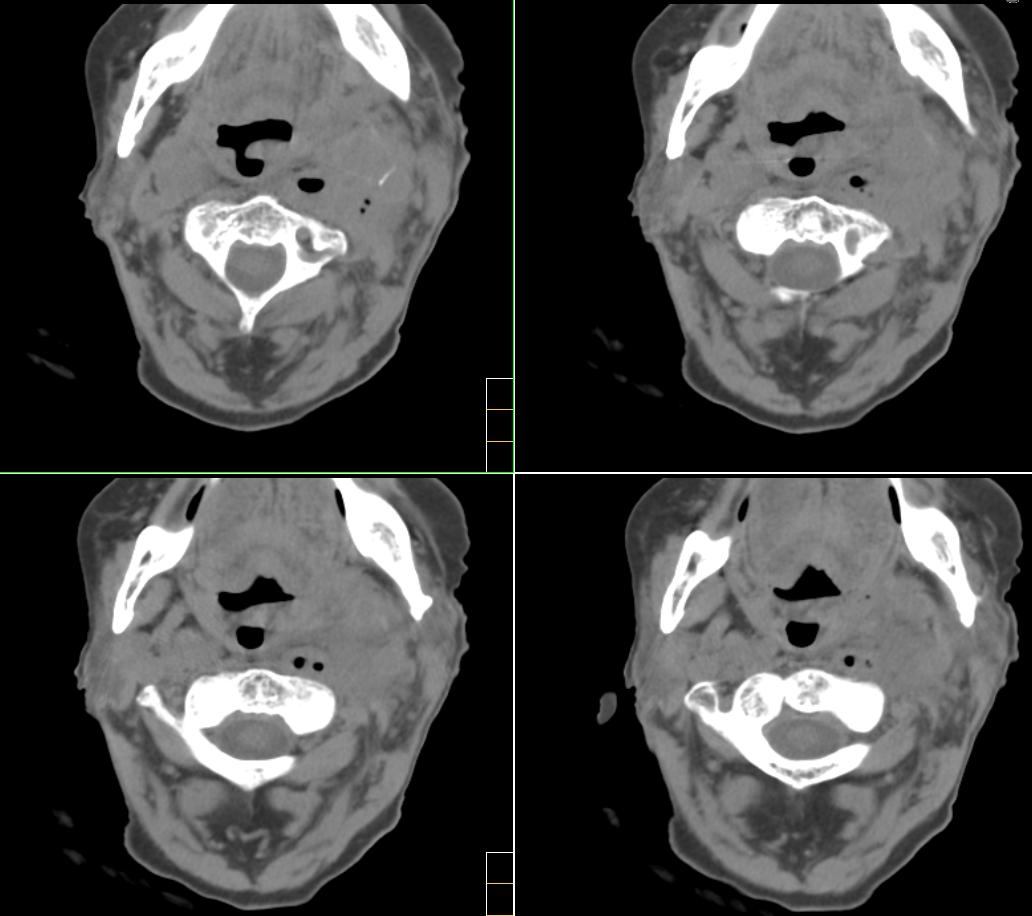

标题: CT4272:求助!颈部血管瘤破裂?

f、72y,左侧颈部发现包块及疼痛1周,彩超提示颈部血管破裂?

考虑血管破裂没什么问题,但颈部这么多积气哪来的?有外伤吗?或颈部脓肿腐蚀血管?

或颈部脓肿侵蚀血管可能性大

左颈部血管增粗,周围软组织肿胀模糊,内有蜂窝状积气影,左侧甲状腺增大,气管受压右移,气管软骨环未受侵。结合病史较短考虑:左颈部脓肿破裂并血管瘤形成,左甲状腺瘤。